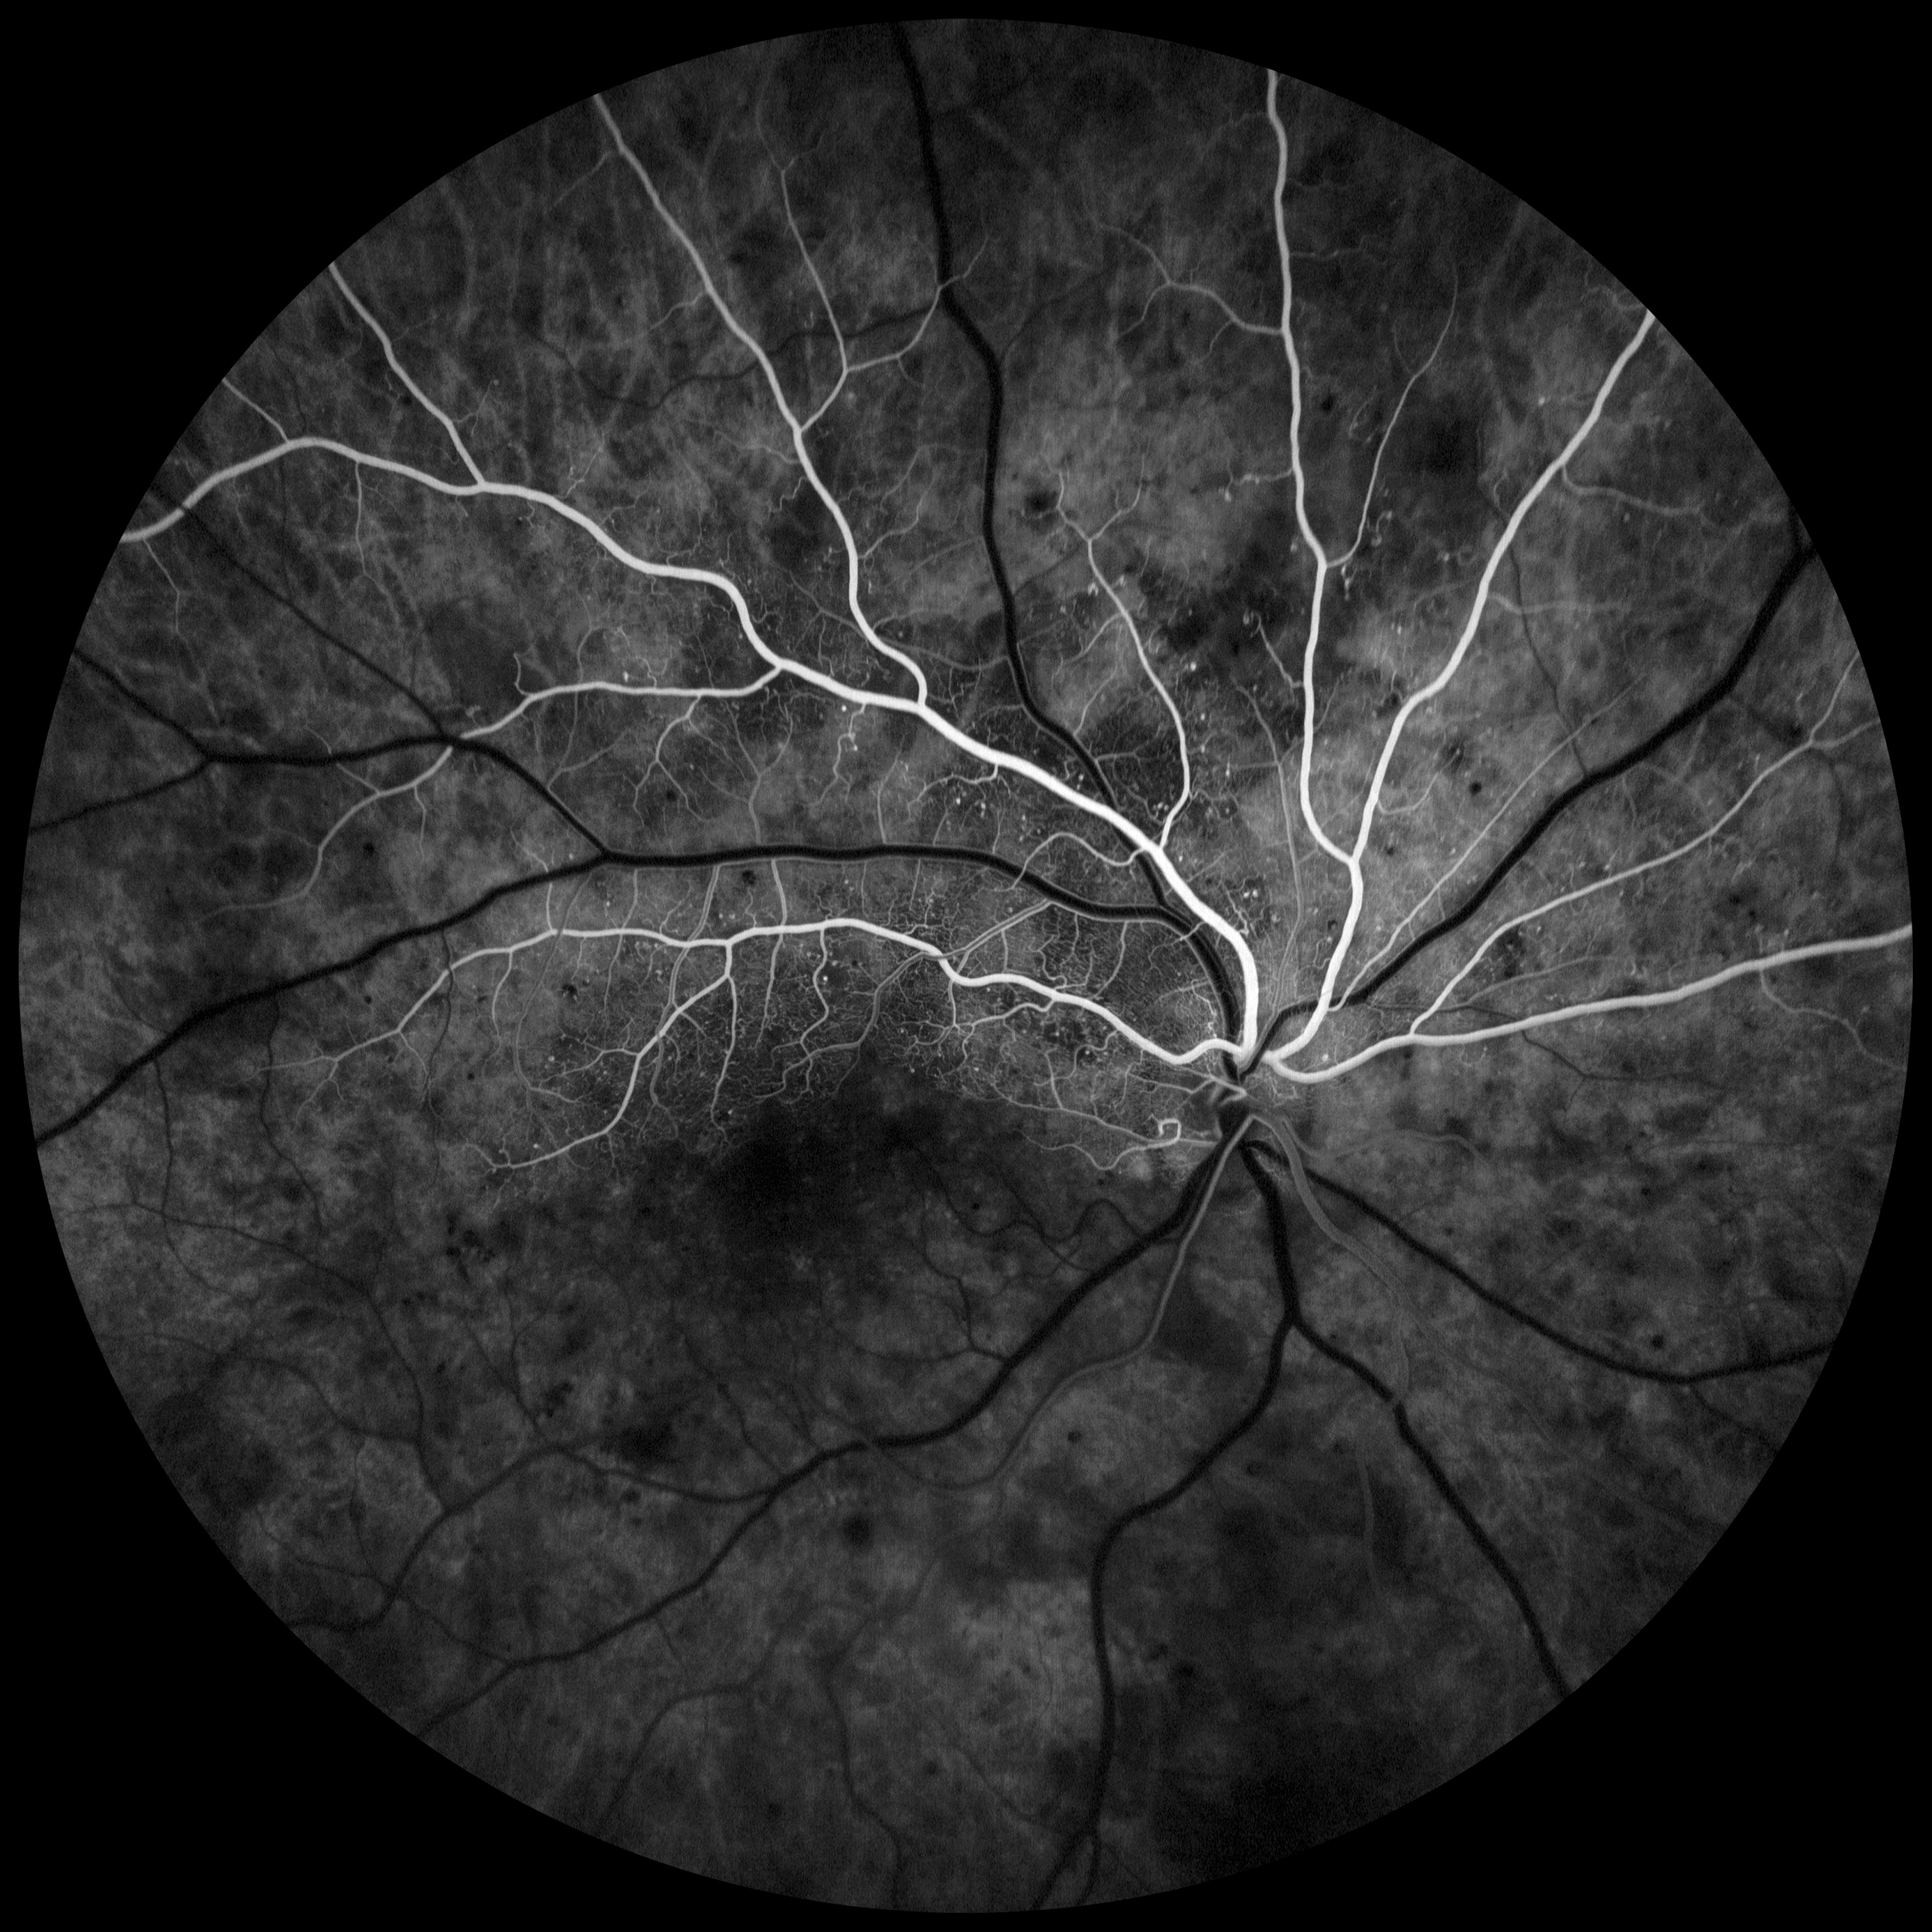

Primer Lugar:Edema Macular Diabético con Retinopatía Diabética No-Proliferativa en la categoría de Angiografía con Fluoresceína